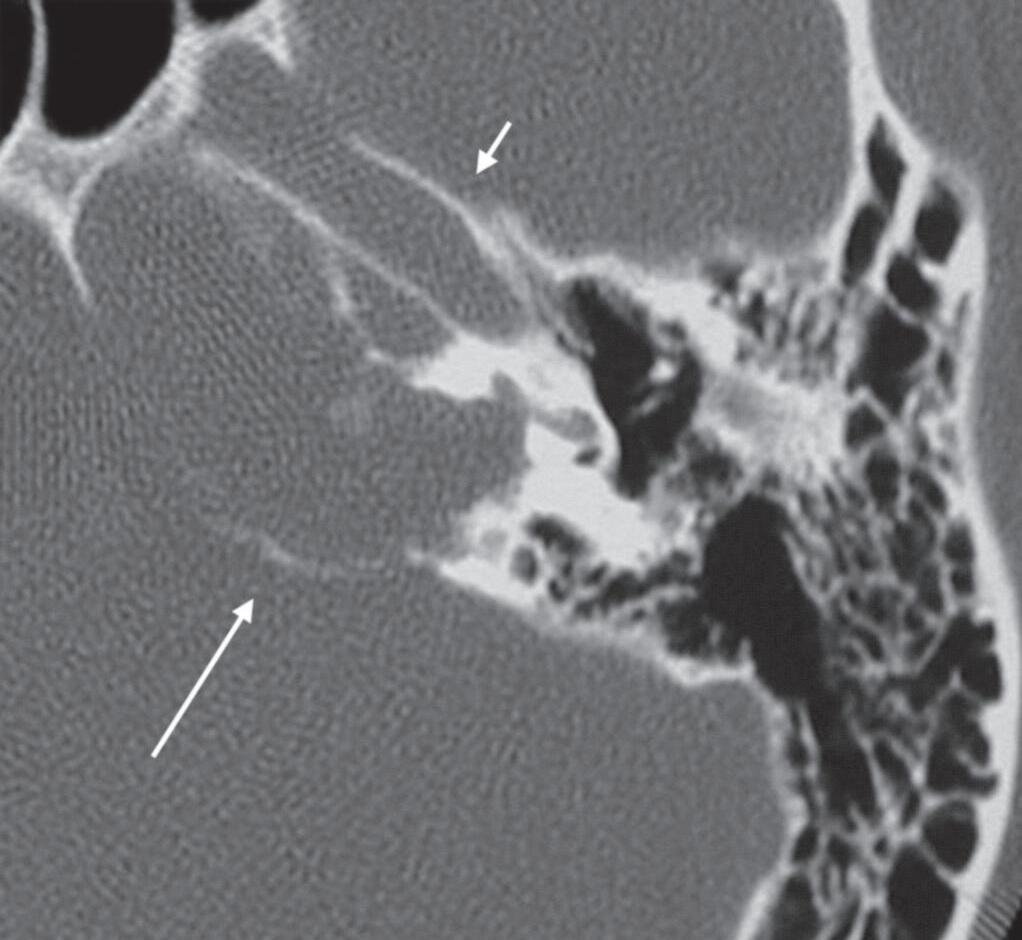

1-15. Granuloma de colesterol no ápice petroso: TC dos ossos temporais: lesão expansiva no ápice petroso com atrofia óssea de pressão de suas paredes (seta longa); canal carotídeo (seta curta).